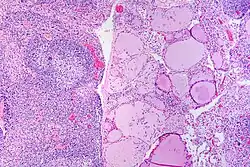

![]() |

Tuberculous lymphadenitis | Caseating granulomatous lesion with areas of amorphous granular eosinophilic necrotic debris known as caseation (on the right half) bordered by collections of epitheloid cells, Langhan giant cells and lymphocytes. | Category: Histopathology of tuberculous lymphadenitis | Tuberculous lymphadentis |